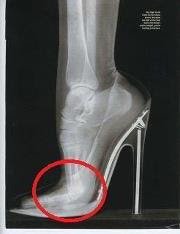

High heels mendorong pusat massa pada tubuh ke depan, membuat pinggul dan tulang belakang tidak lagi sejajar. Dari samping, tubuh akan terlihat melengkung. Hasil studi menemukan bahwa perempuan yang sangat sering memakai hak tingi akhirnya tidak bisa memakai sepatu-sandal yang datar. Hal ini disebabkan otot tendon kaki akan memendek, sehingga otot tumit tidak lagi bisa sejajar dengan jari kaki.

Fakta menunjukan, pada tahun 2010 saja, hampir tiga juta perempuan mengalami cedera kaki akibat pemakaian sepatu ini. Dari kasus-kasus yang terjadi, kebanyakan terkilir atau tendonya robek. Bahkan ada juga sampai terjadi kasus gigi hancur, patah akibat terjatuh saat mengenakan sepatu high heels. Sayangnya laporan ini tetap tidak cukup untuk menghalangi 60 persen dari perempuan yang diwawancarai (untuk studi), untuk memakai hak tinggi. Mereka mengatakan akan terus mengenakan sepatu hak.

Menggunakan sepatu hak tinggi dapat menyebabkan masalah punggung bagian bawah juga. Dokter mengatakan bahwa mereka biasanya dapat tahu dari keselarasan panggul apakah seorang wanita memakai sepatu hak karena tulang pinggul akan terdorong dan akan sering mengeluh sakit leher dan bahu.